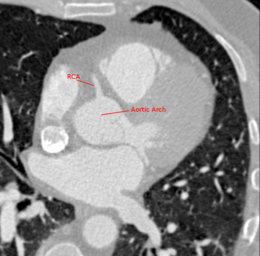

Medical imaging is used for the diagnosis of CAD and for the quantification and grading of stenosis. The extraction of the central lumen line (centerline) of coronary arteries is helpful for visualization purposes, stenosis quantification or further processing steps (e.g. reformatting) [Schaap2009]. This tutorial shows how to use tools based on the Vascular Modeling Toolkit (VMTK) ([Antiga2008]) in 3D Slicer to segment the right coronary artery (A. coronaria dextra, RCA) in a computed tomography angiography (CTA) volume and extract the associated centerline. In particular the segmentation is performed on a CTA dataset which was obtained through the Rotterdam Coronary Artery Algorithm Evaluation Framework ([Schaap2009]). Even if this documentation shows how to establish a work flow between three VMTK in 3D Slicer tools, each of the three documented segmentation steps can be considered as a guide for the individual module.

The initialization step involves the description of a starting model within a region of interest. In the evolution step this initial deformable model then gets inflated to match the contours of the targeted volume. We want to initialize inside the RCA on the vessel enhanced volume from the previous step and then evolve on the original extracted subvolume. INSTRUCTIONS: Initialization: